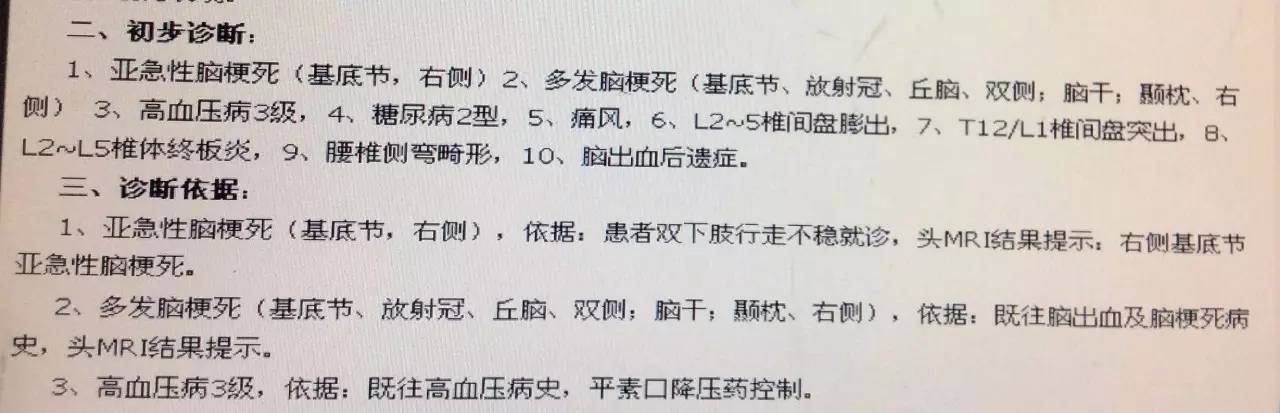

患者:男,47岁,主因“突发行走不稳2天”入院。

现病史:患者2天前无明显诱因突发行走不稳,自行休息后未见缓解,未予以治疗。2天来上述症状无明显缓解,就诊于我院,行头MRI+MRA检查示多发脑梗死、脑萎缩、颅内动脉硬化。家属为求进一步诊治收入住院。

既往:脑梗死病史16年,遗留双眼复视;脑出血9年,未遗留后遗症;痛风病史10年;高血压病史10年;糖尿病病史10年;腰椎椎管狭窄10年,表现行走偏斜,不能长久行走。

辅助检查:

2016-3-6 头MRI+MRA示右侧基底节亚急性脑梗死;双基底节、放射冠、丘脑、脑干、右侧颞枕叶多发脑梗死,部分软化灶形成;脑萎缩改变;MRA符合动脉硬化改变。

患者目前应用阿司匹林100mg/d,硫酸氢氯吡格雷75mg/d,阿托伐他汀钙片20mg/d治疗,系统内科治疗后患者双下肢行走不稳症状较前明显改善。但患者近三日出院发热,考虑肺部感染给予抗生素治疗,于2016-3-16 15:30出现言语不能及进食呛咳。MRI检查提示:双侧基底节、放射冠急性/亚急性腔隙性脑梗死。患者出现新鲜梗死,请帮助分析梗死原因,及下一步诊治方案。